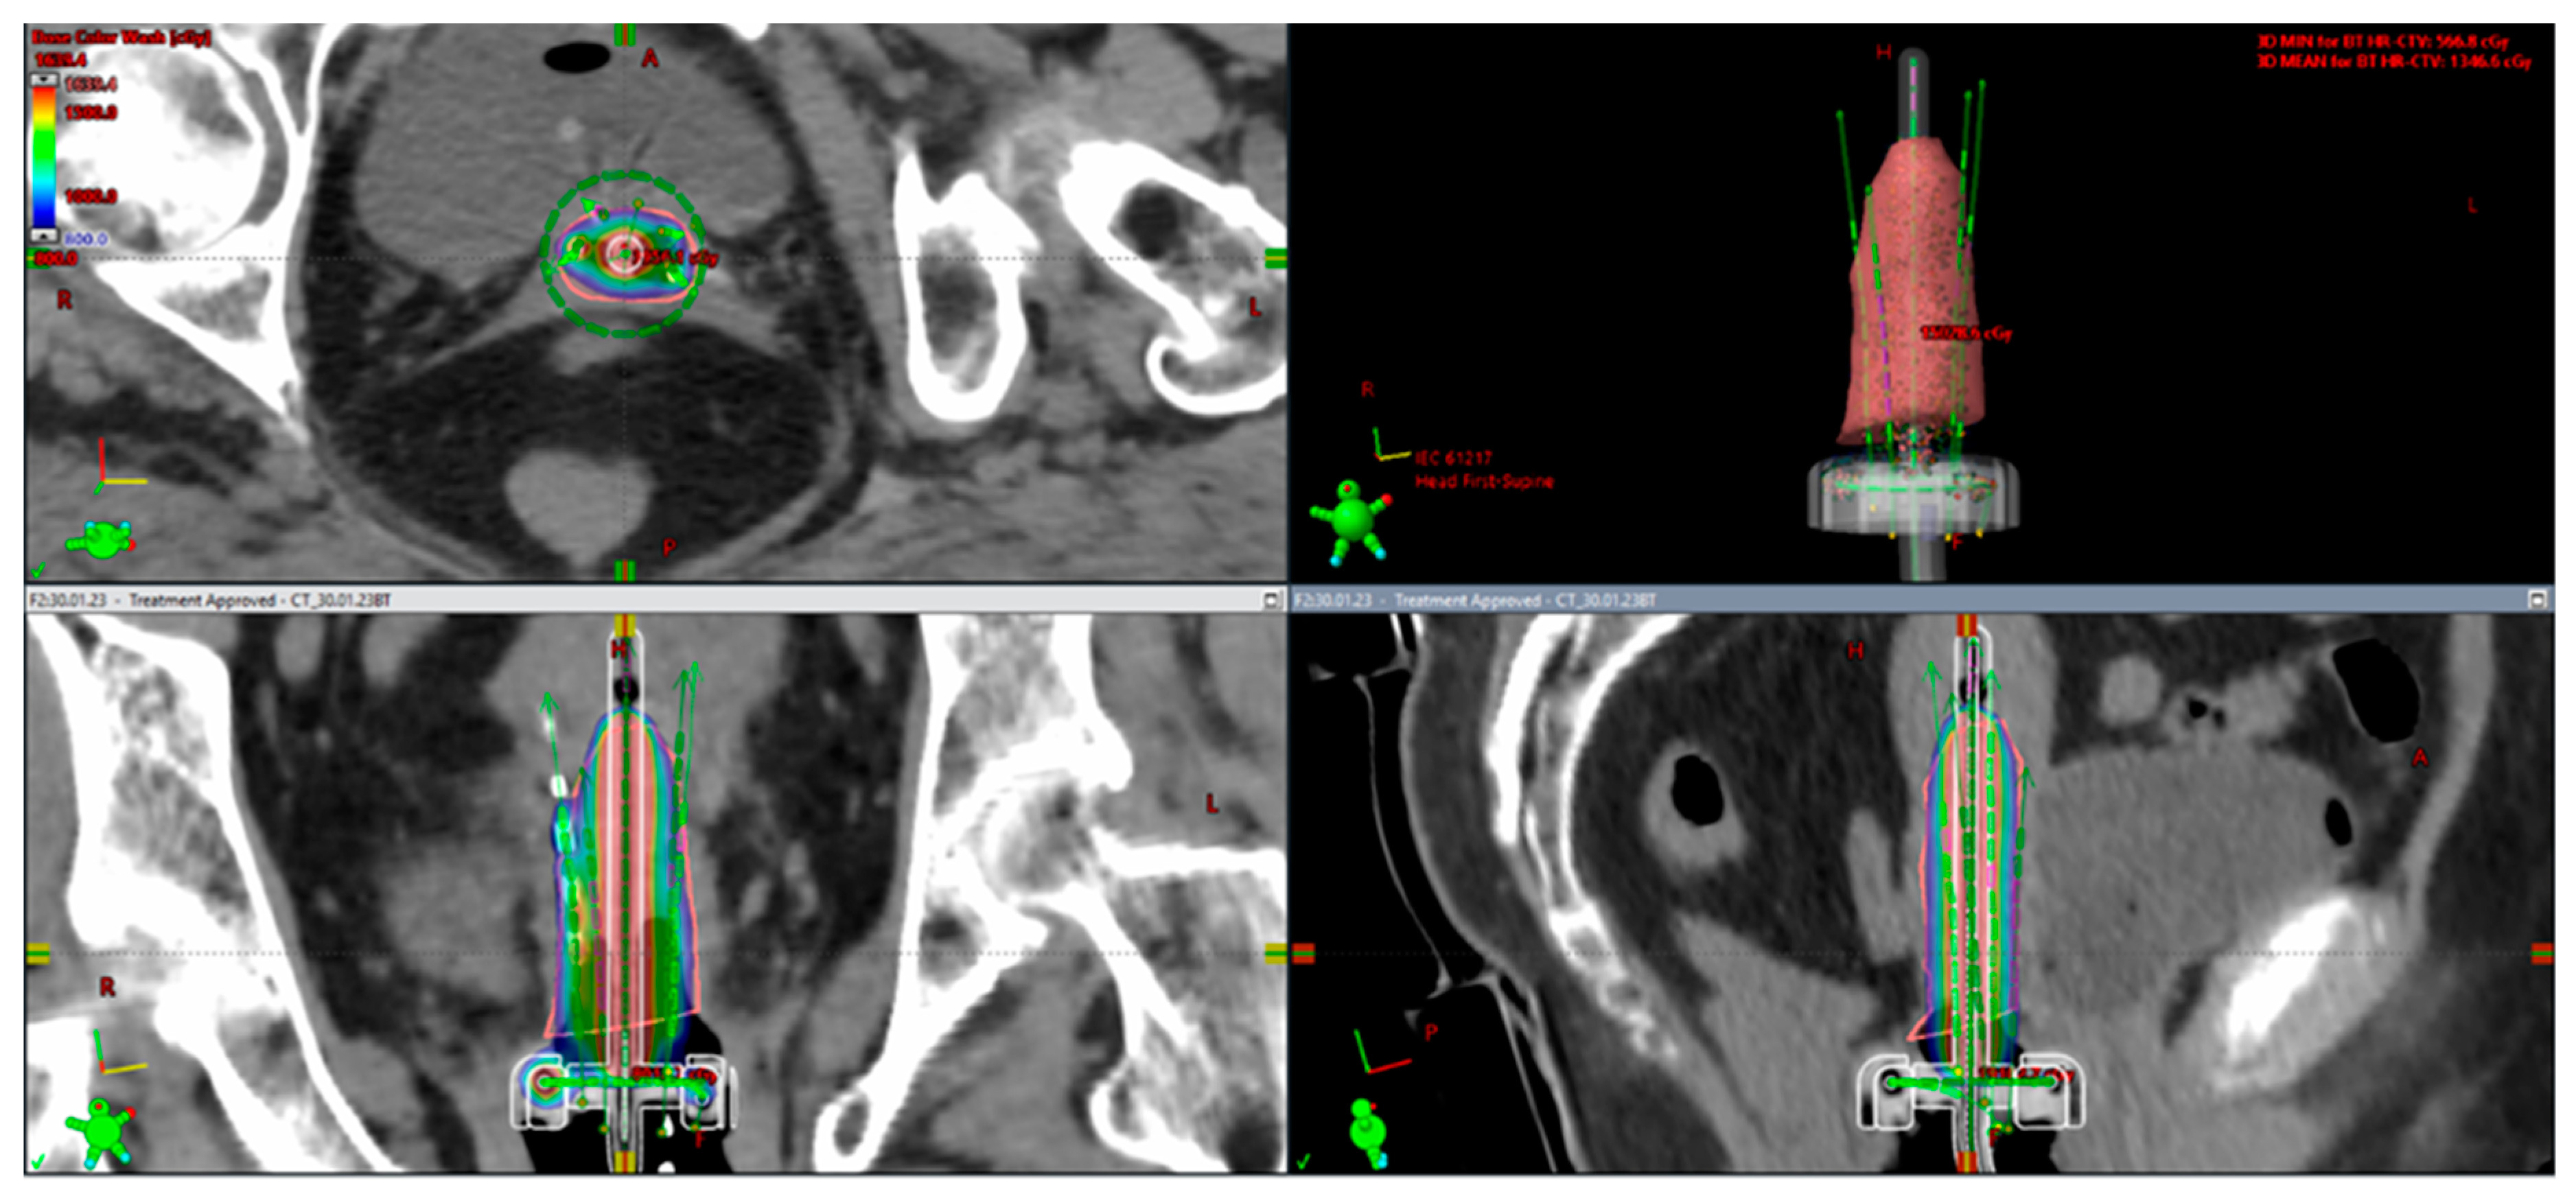

4.1. From 2D Brachytherapy (2D-BT) to 3D Image-Guided Adaptive Brachytherapy (3D-IGABT)

4.2. Adaptive Brachytherapy

4. Advances in Brachytherapy